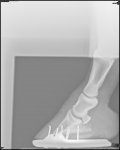

Xrays show there is a small amount of rotation in the left fore. Right fore is fine. I don’t have them on email yet but will share them when I do.

It’s minimal in the LF and vet hopeful it can be corrected with trimming and shoeing etc. Her toe on the LF is much longer than the RF so the rotation might even be less than it looks once the toe corrected. Sole depth looks good.

Xrays attached. You can see that one has some rotation and much more toe-that’s the one she was lame on.